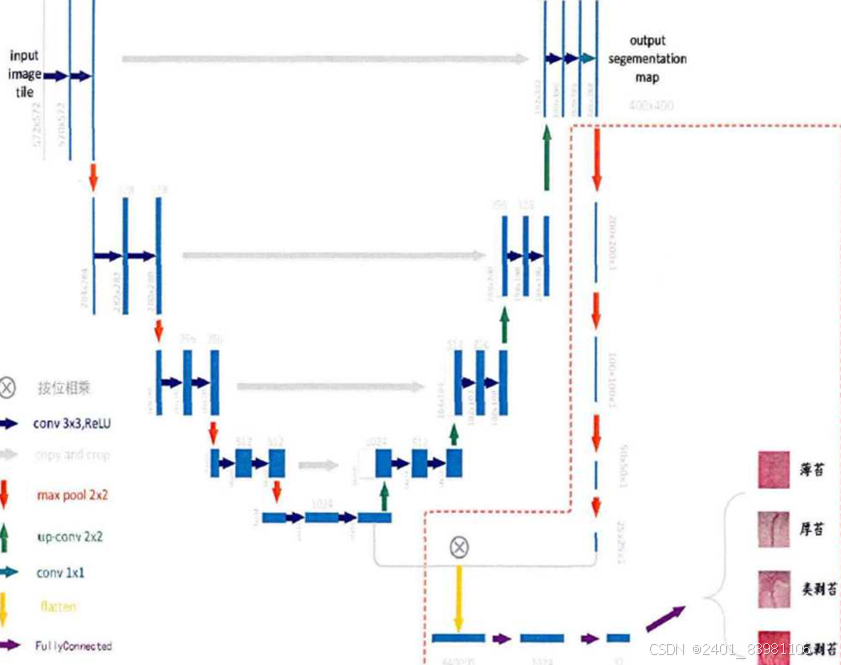

改进的h-Unet架构:

包包括:图像正则化,参数设置(学习率,交叉验证折数)

采用h-Unet解决Unet没有全连接层问题(对应可视化图)

一篇论文提出的方法实现:

步骤1 .:数据获取并对数据进行编码、归一化处理形成待检测数据,并制作包含训 练集与验证集的数据集。1 .1使用PH试纸或者标准比色卡放置于舌头旁边,以提供标准参考系1 .2使用相机或者手机等拍摄设备拍摄舌头与PH试纸或标准比色卡的照片,保存, 将已确定的标准化舌苔类别图像人工分类分别放入对应的目录中。 1 .3数据编码,将1 .1中获取的数据类别标签进行one-hot编码,健康舌苔图像、不 健康舌苔图像分别对应01 ,10两位二进制数。步骤2:利用Keras搭建深度卷积神经网络。 2 .1使用基于tensorflow的Keras,调用其内置函数,搭建一个CNN2D的网络,激活 函数使用relu。2 .2在2 .1的基础上,向其添加一层最大池化层。2 .3反复2 .1-2 .2操作,添加若干组CNN2D与最大池化层。2 .4在2 .3的基础上,向其添加一层平坦层。2 .5在2 .4的基础上,向其添加一层全连接层,激活函数使用relu。2 .6反复2 .5,向其添加若干层全连接层。2 .7在2 .6基础上,向其添加输出层,2个神经节点,激活函数使用softmax,完成网 络搭建。步骤3:将步骤1所划分的训练数据输入步骤2搭建的神经网络,对神经网络进行训 练。3 .1将步骤1中的到的两类数据混合并对应好其label,输入步骤2得到的网络中, 其中数据总量的80%用于训练,10%用于验证,10%用于测试。3 .2训练若干个epoch后,验证准确率不再上升,即停止训练,用测试集测试其准确 度。3 .3反复调参,直到得到最优模型。 步骤4:深度学习模型训练完成后保存权重参数,并利用该权重对测试数据进行识别分类。4 .1保存权重与模型结构,对用户数据进行预测。